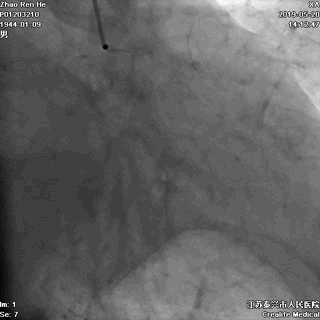

LCX提供侧枝逆向供应右冠

侧枝血管粗,弯曲小而少

IVUS实时指导寻找LAD入口

开通后的LAD